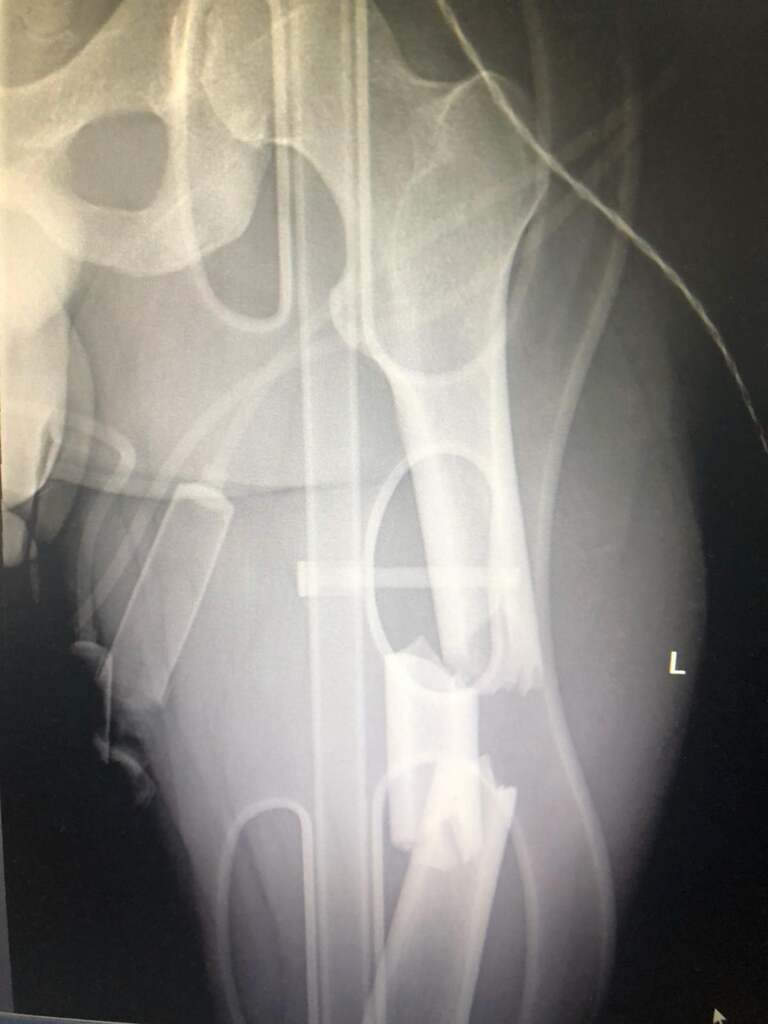

Cu răni pe tot corpul, polițistul care avea atunci 30 de ani a ajuns la Spitalul Județean, unde a fost operat. Medicii au constatat că Octavian Popa avea dublă fractură de femur, fractură de tibie și peroneu, ligamente și meniscul rupte, mușchii gambei smulși și un genunche făcut „praf”. Ca să-i fie vindecate rănile, agentul a primit 120 de zile de îngrijiri medicale, dar, cu recuperare cu tot, a stat în concediu medical 300 de zile.